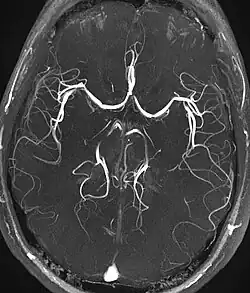

Magnetic resonance angiography (MRA) generates pictures of the arteries to evaluate them for stenosis (abnormal narrowing) or aneurysms (vessel wall dilatations, at risk of rupture). MRA is often used to evaluate the arteries of the neck and brain, the thoracic and abdominal aorta, the renal arteries, and the legs (called a "run-off"). A variety of techniques can be used to generate the pictures, such as administration of a paramagnetic contrast agent (gadolinium) or using a technique known as "flow-related enhancement" (e.g., 2D and 3D time-of-flight sequences), where most of the signal on an image is due to blood that recently moved into that plane (see also FLASH MRI).[53]

Techniques involving phase accumulation (known as phase contrast angiography) can also be used to generate flow velocity maps easily and accurately. Magnetic resonance venography (MRV) is a similar procedure that is used to image veins. In this method, the tissue is now excited inferiorly, while the signal is gathered in the plane immediately superior to the excitation plane—thus imaging the venous blood that recently moved from the excited plane.[54]

| Magnetic resonance angiography (MRA) and venography | Time-of-flight | TOF | Blood entering the imaged area is not yet magnetically saturated, giving it a much higher signal when using short echo time and flow compensation. | Detection of aneurysm, stenosis, or dissection[94] |

|

| Phase-contrast magnetic resonance imaging | PC-MRA | Two gradients with equal magnitude, but opposite direction, are used to encode a phase shift, which is proportional to the velocity of spins.[95] | Detection of aneurysm, stenosis, or dissection (pictured).[94] | ![]() (VIPR) |